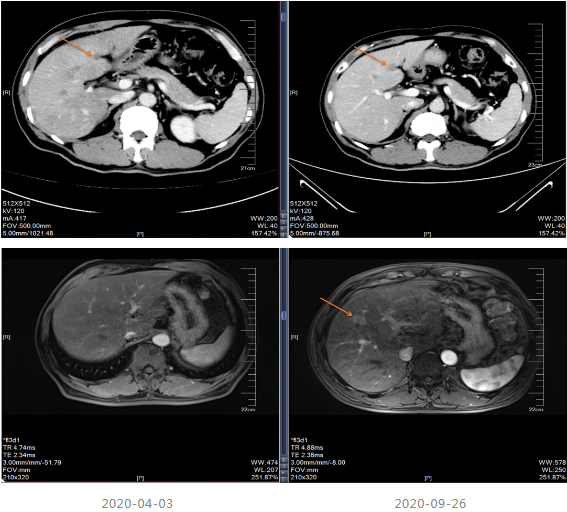

2019-03-14行上腹部增强CT,显示肝内散在的多发圆形稍低密度灶,大小不等,边界欠清晰,较大者直径约5.2cm,其内密度不均,增强扫描病灶周边有强化,内部有更低密度区液化坏死区,考虑转移瘤;胆囊多发结石;双肾多发结石,直径小于0.2cm;扫描范围内结肠肝区管壁增厚,管腔狭窄,增强扫描可见明显强化。

局部治疗:2020-09-26复查MRI提示部分病灶较前缩小,部分增大,于2020-10-22至武汉同济医院行“肝脏病灶微波消融术”,后继续口服卡培他滨至2021-5。